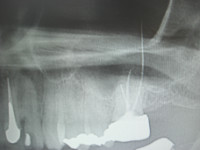

この症例は左上6番部に鈍痛があるとのことで来院された患者様でした。

CTにて精査させて頂きました所6番の遠心頬側根、根尖より根充用のポイントが押し出されてきており、上顎洞内に大きく突出しておりました、これが上顎洞炎併発の原因であると考え、頬側より小さく骨窓を開窓しまして、ポイントを除去し、同時にこれもまた上顎洞内に突出している歯根の尖端を切除しオペ終了といたしました。